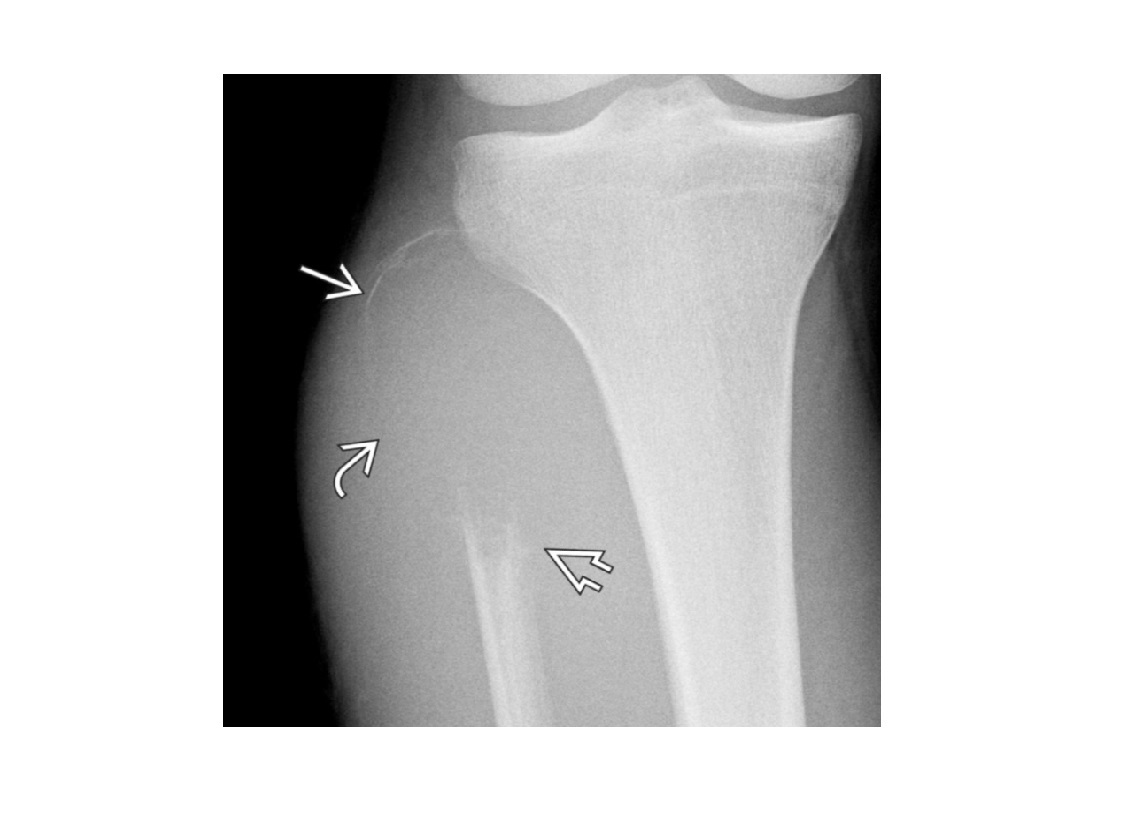

Segond fracture

Lateral tibial plateau

Associated with ACL tear (75%) and internal rotation

MR SL = Medial Reverse Lateral Segond

Reverse Segond fracture

Medial tibial plateau

Associated with PCL tear with external rotation. Associated with medial meniscus injury.